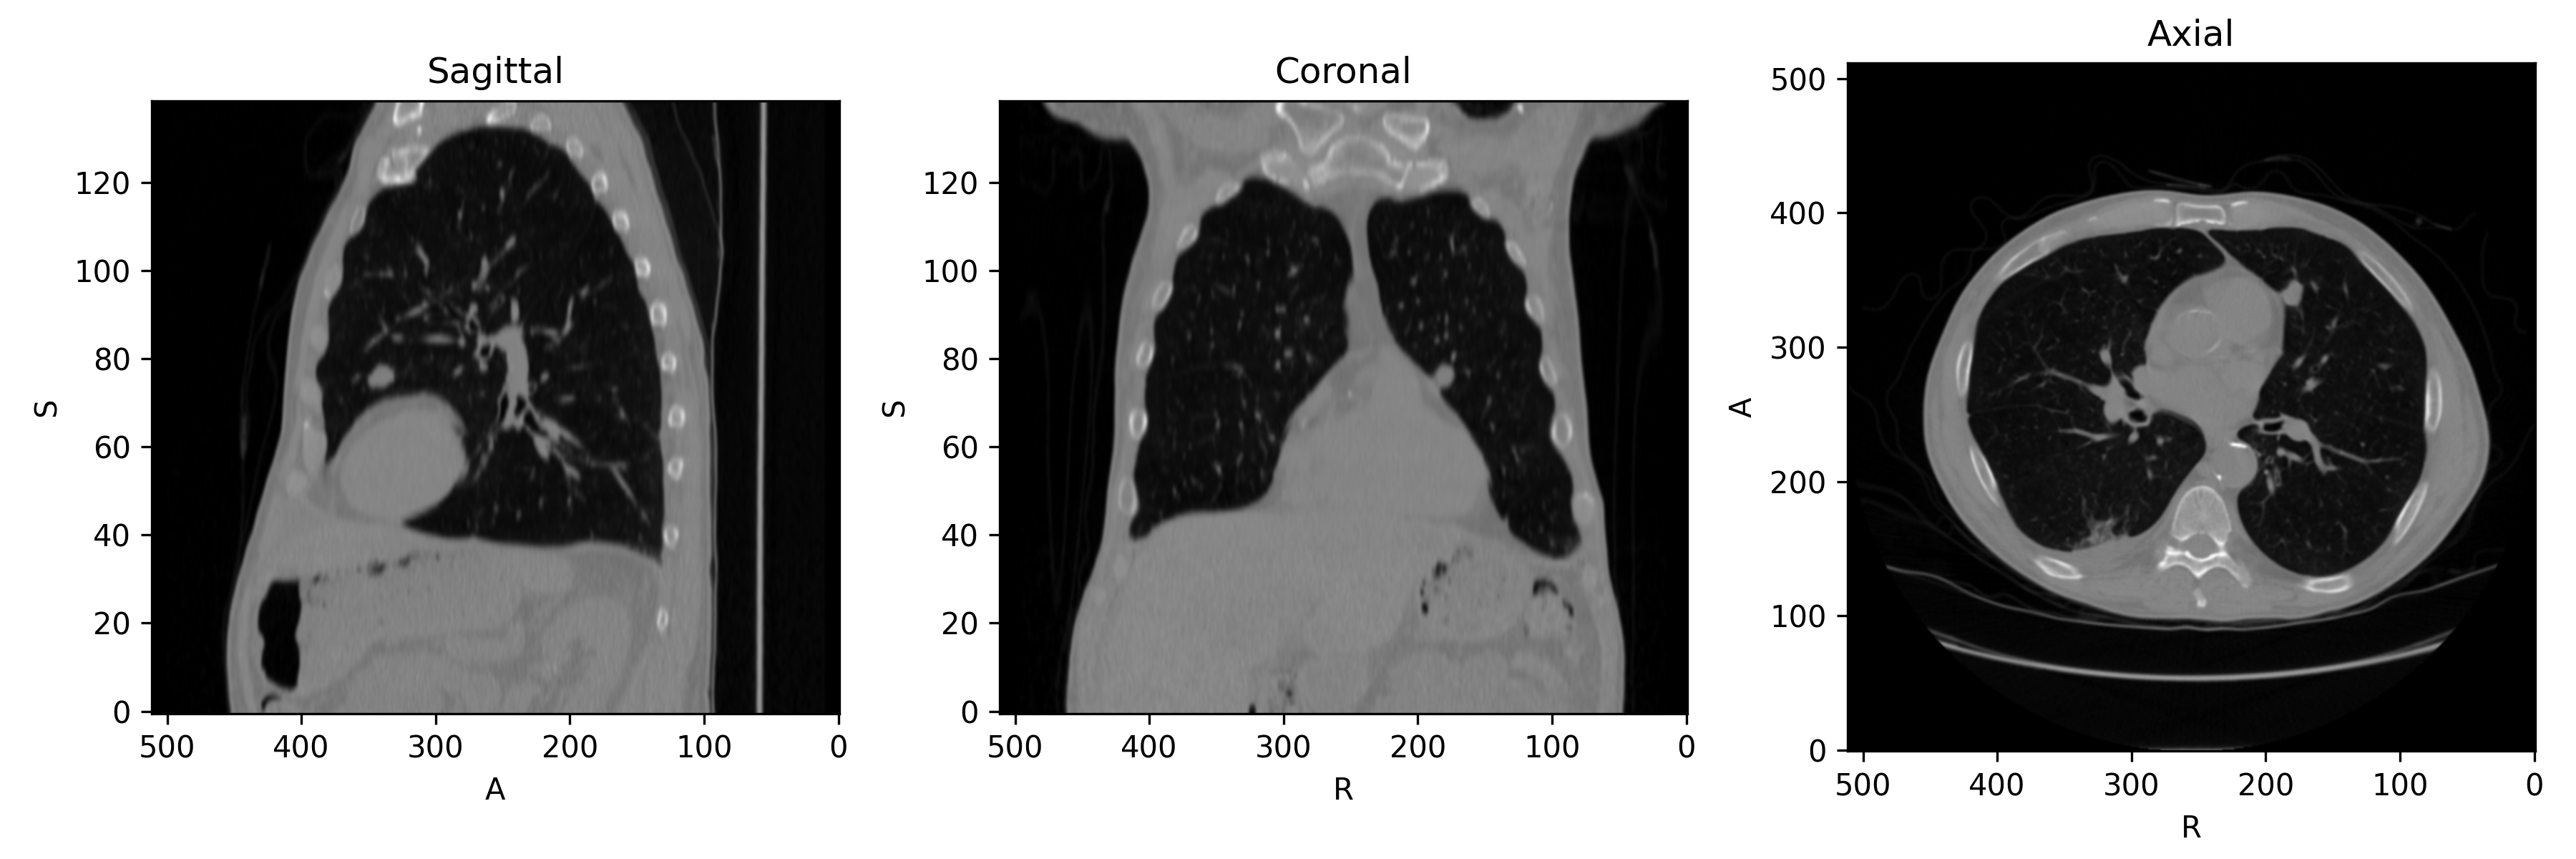

First, let's get a 3D chest CT we can use for demonstration. The plotted slices intersect a lung nodule near the heart.

The image looks like this:

Input CT